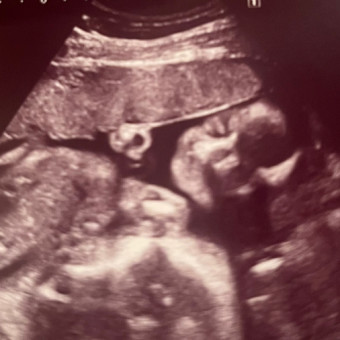

Paige and Eli’s Baby registry

Paige Enstall & Elijah Snyder

Saint James, MO

August 10, 2025

💙 Our baby boy will be here in August 💙